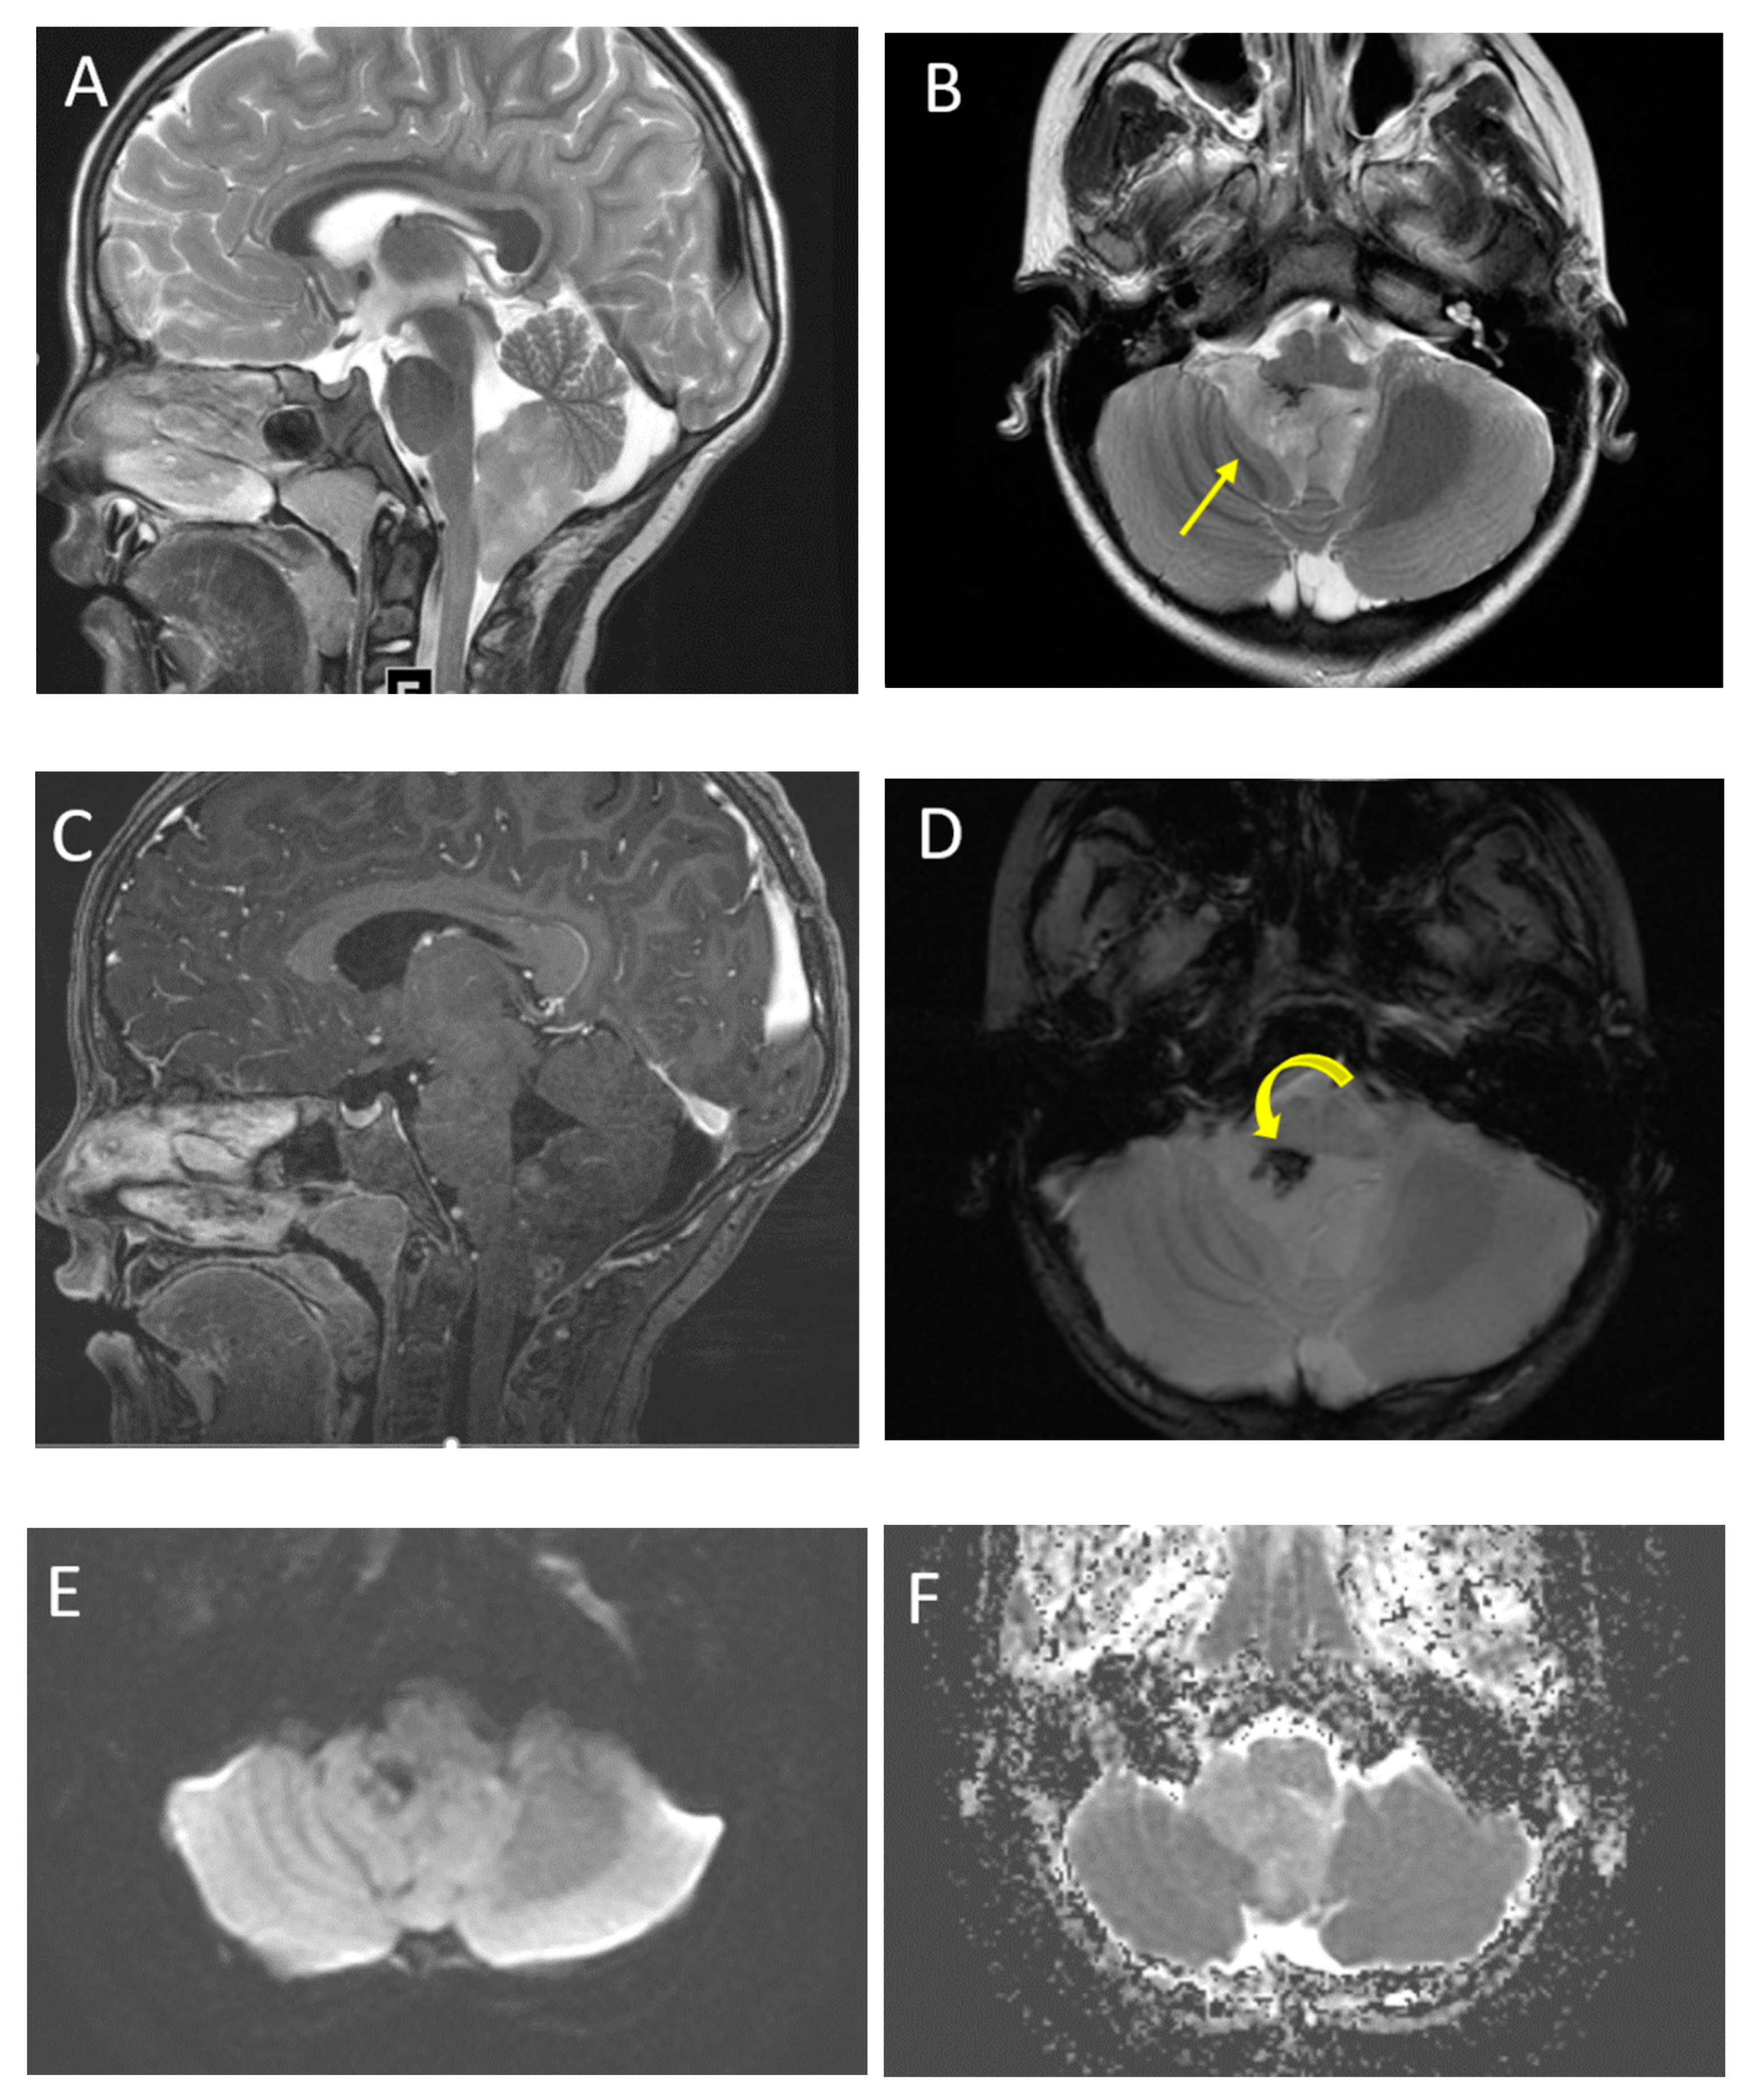

| Posterior fossa ependymoma | Fourth ventricle (PFB) or cerebellopontine angle (PFA) | Heterogeneous mass Calcifications common Intermediate diffusion (between medulloblastoma and pilocytic astrocytoma) Usually enhancing High myo-inositol on MRS |